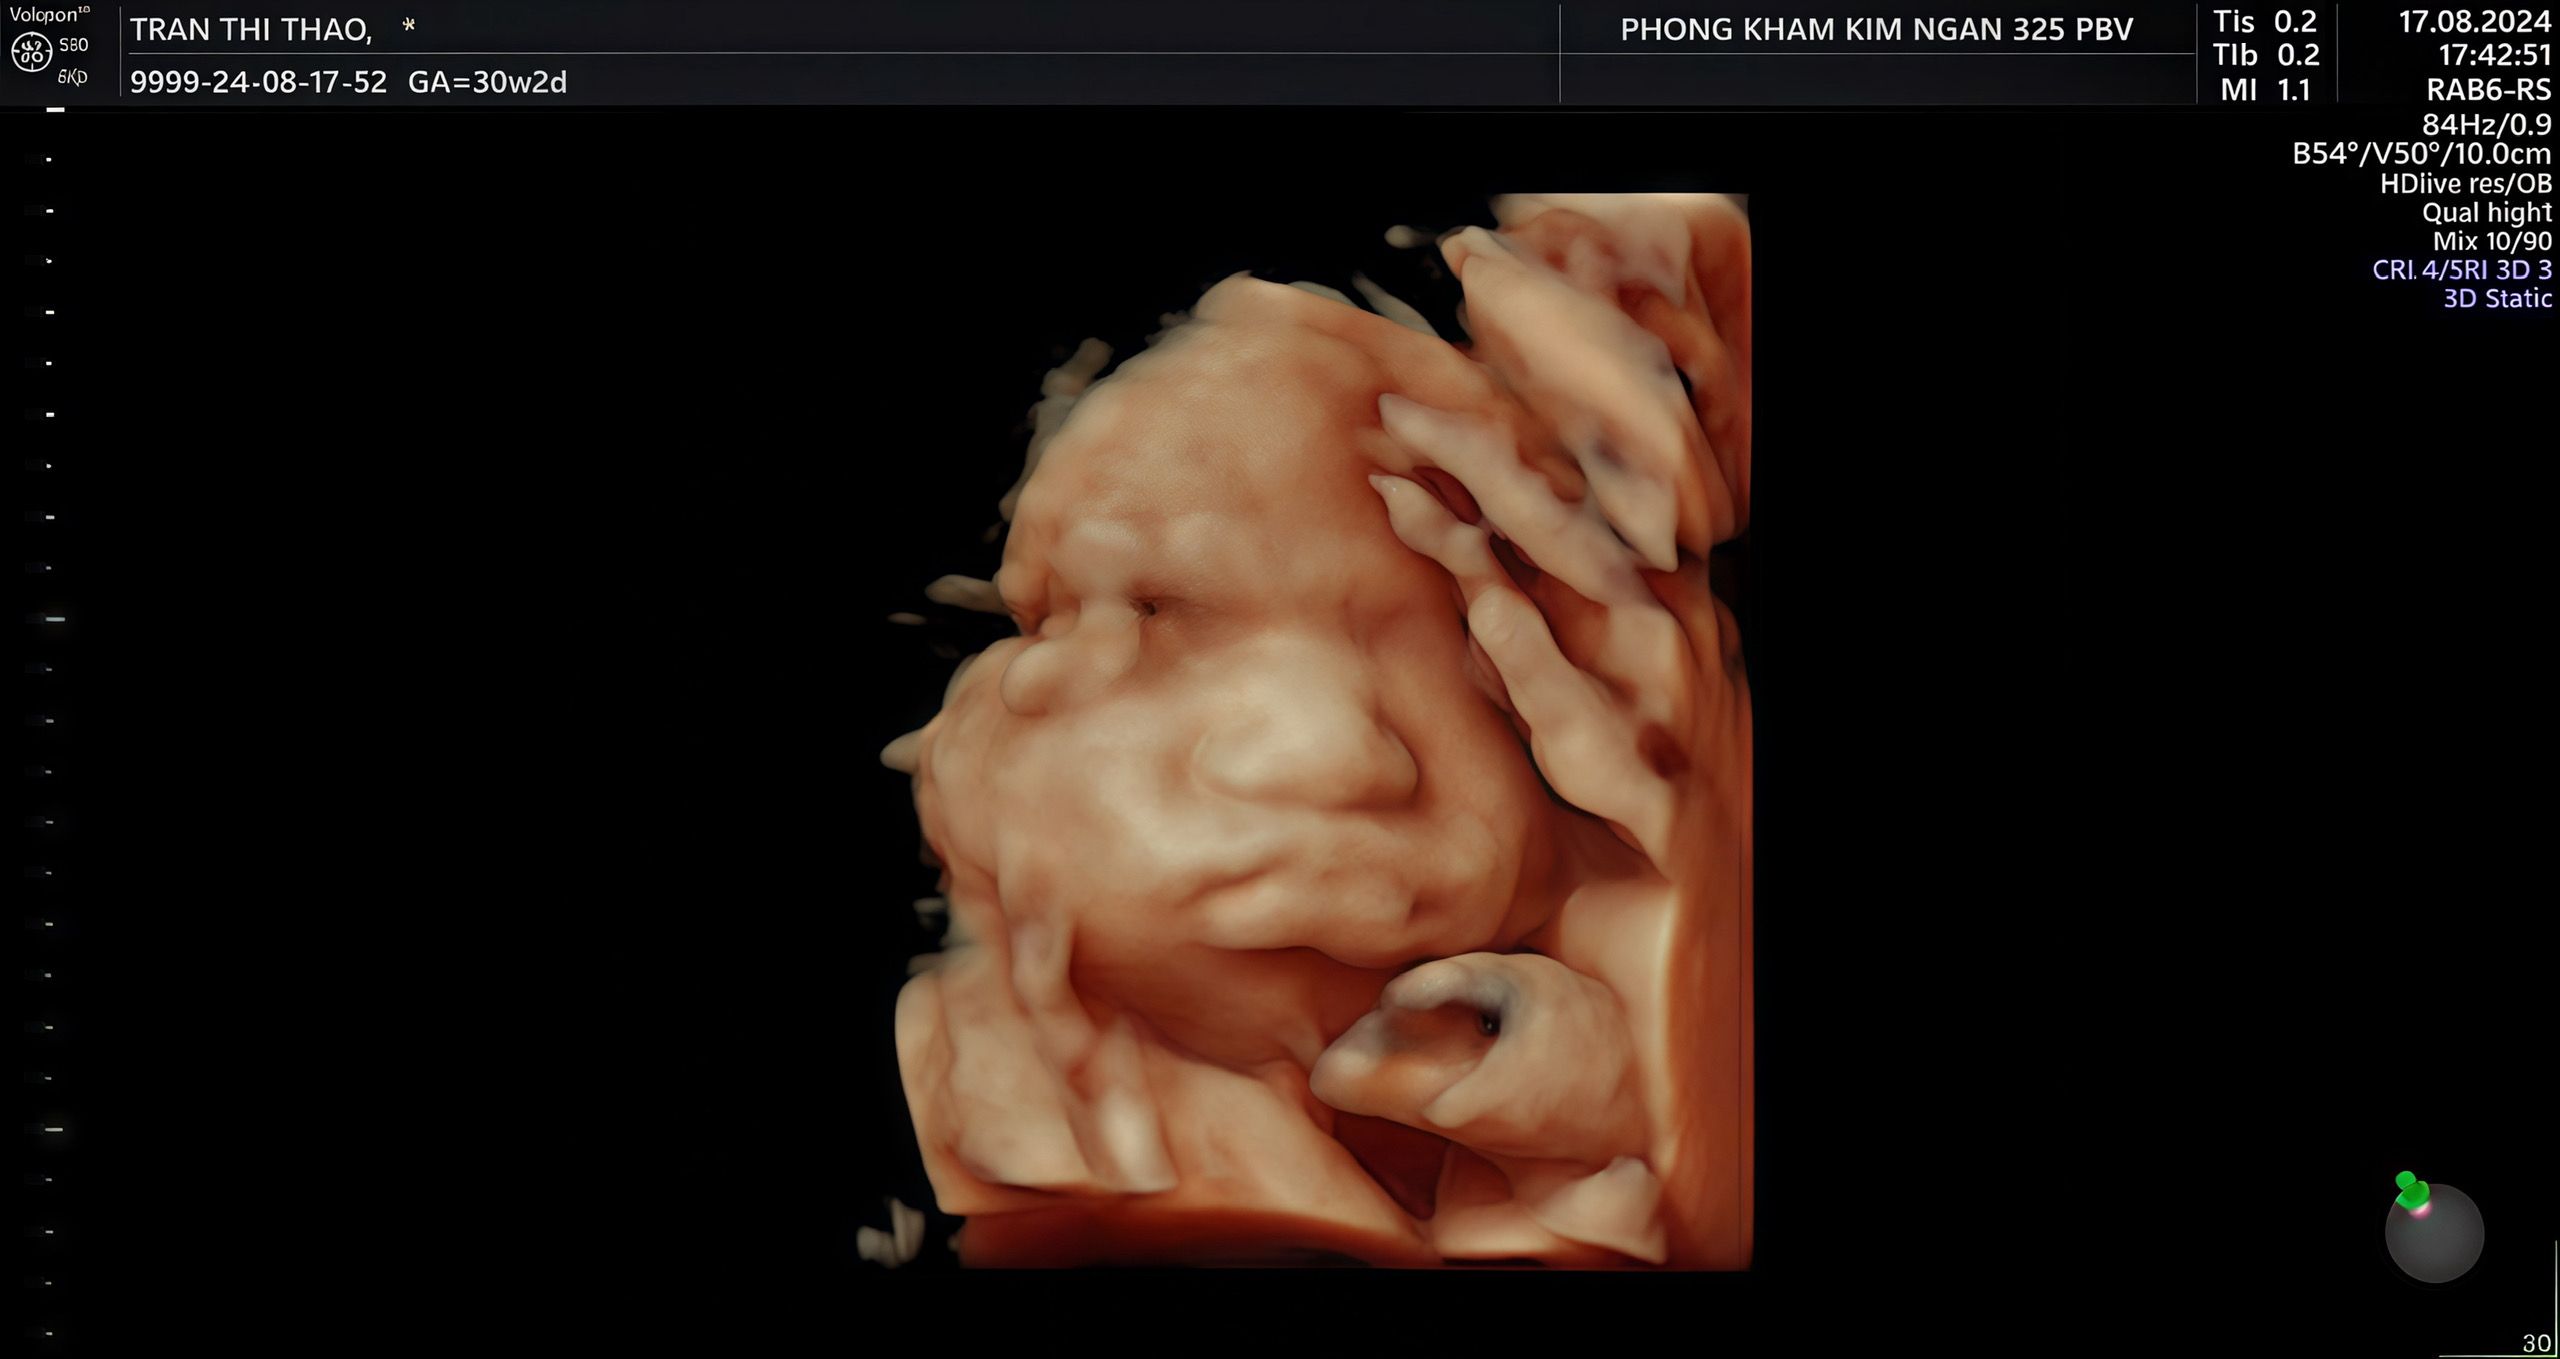

Lần đầu bố mẹ được gặp con

5 giờ 15 phút sáng ngày 21 tháng 10 năm 2024 — khoảnh khắc ấy, có lẽ suốt đời cha sẽ không bao giờ quên. Cả căn phòng sáng lên trong ánh đèn trắng, mẹ con mệt nhoài sau những giờ vượt cạn, còn cha thì đứng đó, tim đập mạnh hơn bao giờ hết. Rồi tiếng khóc đầu tiên của con vang lên — tiếng khóc nhỏ bé nhưng đủ khiến cha bật khóc theo.

Cha nhìn thấy con, bé xíu, đỏ hồng và yếu ớt… mà sao lại mạnh mẽ đến thế. Cả thế giới của cha như dừng lại trong giây phút đó. Cha nắm tay mẹ, đôi tay run run không nói nên lời, chỉ biết nhìn hai mẹ con mà nước mắt cứ trào ra — những giọt nước mắt của hạnh phúc, của biết ơn, của một tình yêu lớn lao vừa hình thành.

Từ giây phút ấy, cha biết cuộc đời mình đã có thêm một lý do để cố gắng, để sống tốt hơn từng ngày. Con chính là món quà quý giá nhất mà cuộc đời ban tặng, là bình minh đẹp nhất trong lòng cha — đến đúng lúc 5 giờ 15 phút sáng hôm ấy.